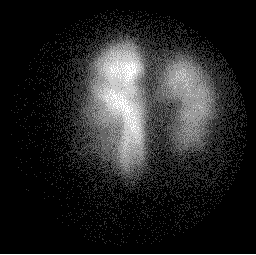

Posterior Perfusion Posterior Ventilation

perfusion1.gif (8591 bytes) vent1.gif (8676 bytes)